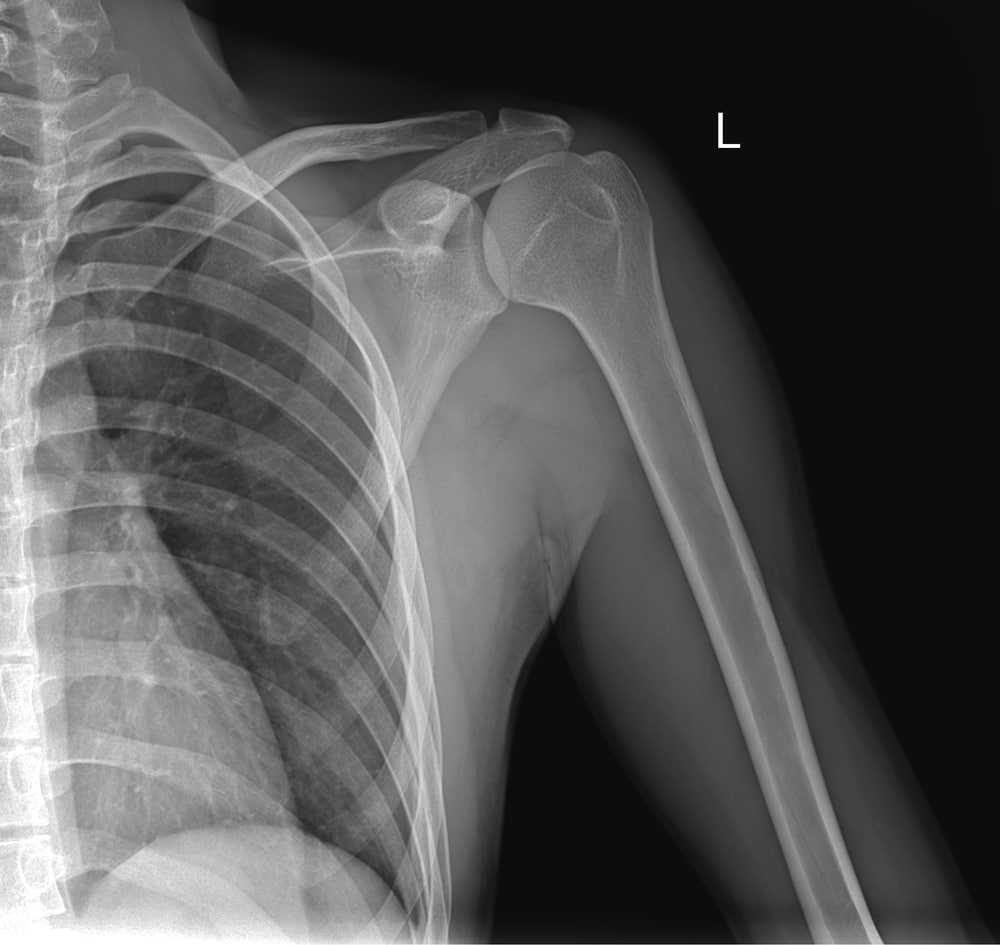

Your surgeon will examine your shoulder, review your medical history, and order imaging tests such as X-rays, a CT scan, or an MRI to get a detailed look at your bones and soft tissues. These findings guide the best treatment plan for you.